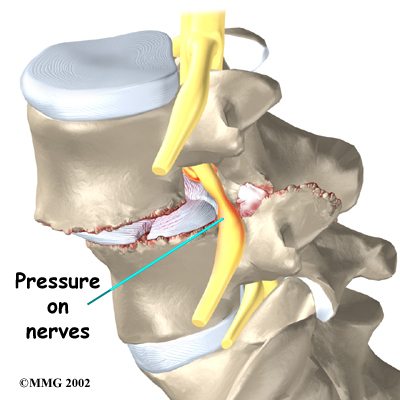

Slippage can also cause nerve compression. Nerve compression is a result of . As the spine slips forward, the nerves may be squeezed where they exit the spine. This condition also reduces space in the spinal canal where the vertebra has slipped. This can put extra pressure on the nerve tissues inside the canal. Nerve compression can cause symptoms where the nerve travels and may include numbness, tingling, slowed reflexes, and muscle weakness in the legs.

Nerve pressure on the cauda equina (mentioned earlier), the bundle of nerve roots within the lumbar spinal canal, can affect the nerves that go to the bladder and rectum. When this happens, bowel and/or bladder function can be affected. The pressure may cause low back pain, pain running down the back of both legs, and numbness or tingling between the legs in the area you would contact if you were seated on a saddle.

When the vertebra slips forward, the nearby nerves that exit the spine can become pinched or irritated. In addition, the size of the spinal canal in the problem area shrinks, placing pressure on the nerves inside the canal. To fix this, the lamina of the bony ring is removed to ease pressure on the nerves. The procedure to remove the lamina and release pressure on the nerves is called . Decompression alone is usually not advised. Studies show much better results when the operation is combined with a fusion of the involved vertebrae (see below).

A spinal fusion is normally done immediately after laminectomy for spondylolisthesis. The fusion procedure is designed to fuse the two vertebrae into one bone and stop the slippage from worsening. The fusion is used to lock the vertebrae in place and stop movement between the vertebrae, easing mechanical pain. When combined with laminectomy surgery (mentioned earlier), fusion helps relieve nerve compression.